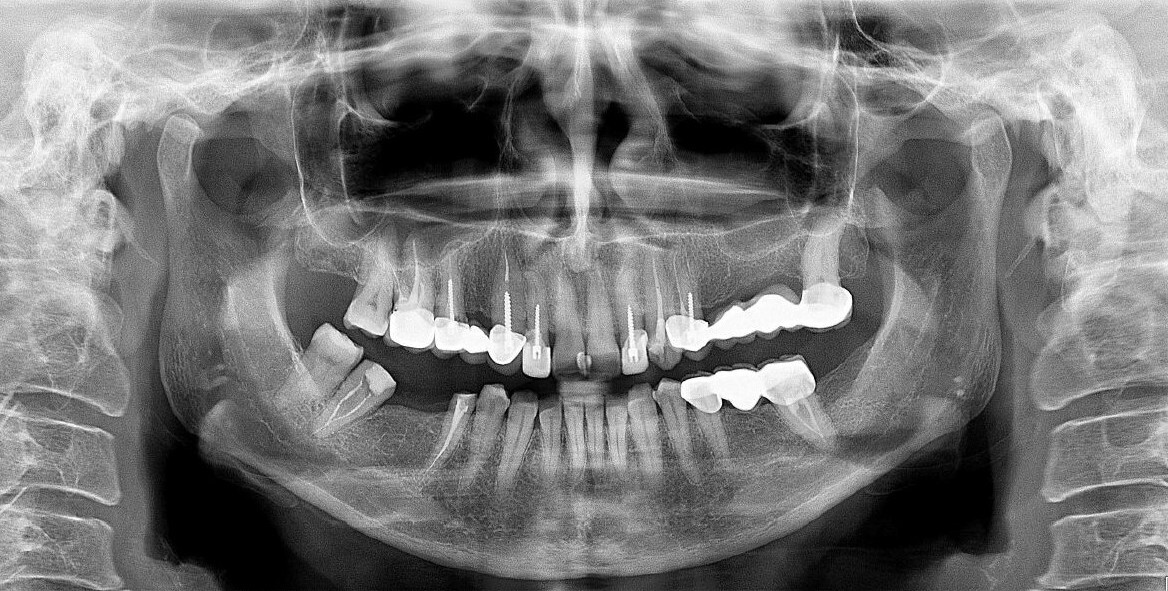

Двухмерный панорамный снимок зубов.

Скриншот каждого корня (канала). Подробное описание. Коронка, канально-корневая система, периапикальные ткани, пародонтальный статус. Скриншоты ВНЧС с измерениями. Описание положение головок, структуры, формы, размеров. Описание всех измененных структур ЧЛО (зубы, пазухи, кость).

Скриншот каждого корня (канала). Подробное описание. Коронка, канально-корневая система, периапикальные ткани, пародонтальный статус. Скриншоты ВНЧС с измерениями. Описание положение головок, структуры, формы, размеров.

Скриншот каждого корня (канала). Подробное описание. Коронка, канально-корневая система, периапикальные ткани, пародонтальный статус.